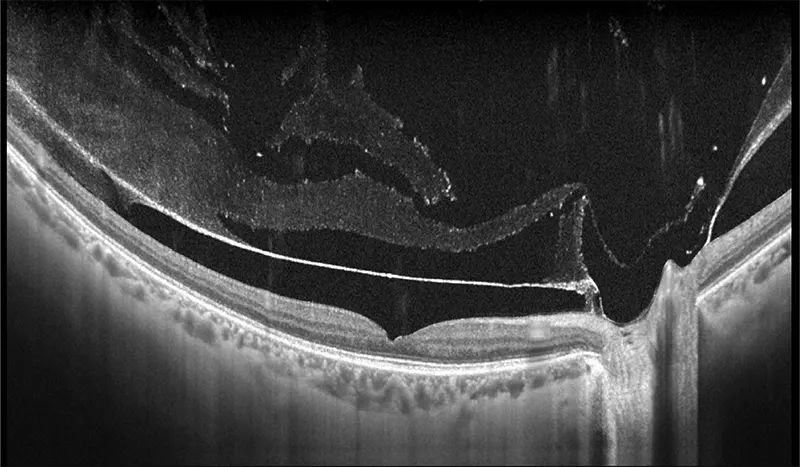

Galería OCTs del TowardPi Yalkaid